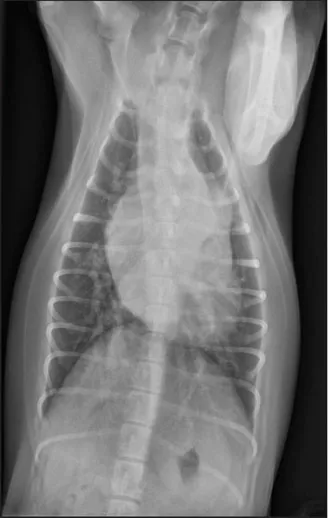

CASE 1.1 A 7-year-old neutered male Labrador Retriever who was hit by a car. You obtain these thoracic radiographs: Figs. 1.1a, b, left and right lateral projections, respectively; Figs. 1.1c, d, ventrodorsal and dorsoventral projections, respectively.

1.1c